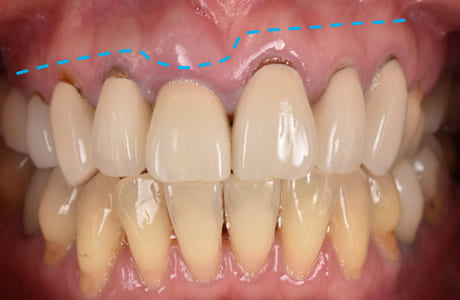

こちらは、歯周外科手術の前と後の比較写真です。

術前と比べて、歯ぐきの位置が整い、歯が自然に長く見えるようになっているのがわかります。

これは歯ぐきのバランスを整えることで、歯の見え方をより美しく改善した結果です。